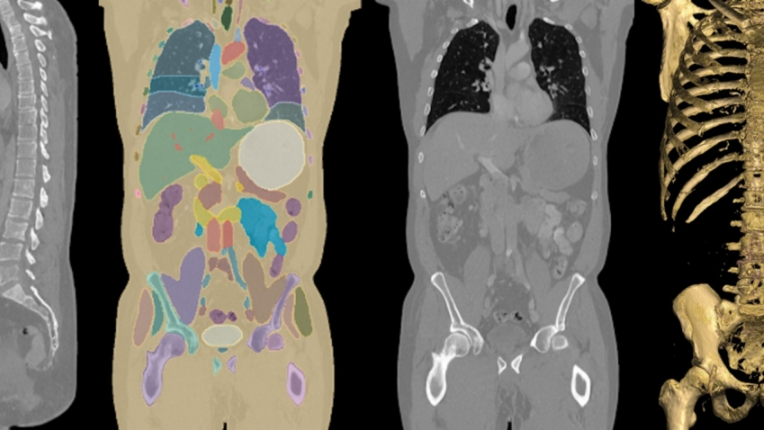

NVIDIA’s AI image analysis and inference solutions empower developers and researchers to perform real-time image analysis, enhance image interpretation, and conduct precise image segmentation and quantitative analysis. Leveraging NVIDIA’s advanced tools and platforms (including GPUs and SDKs), these solutions deliver high-performance inference to speed up medical imaging workflows. To bridge the gap between AI development and production, NVIDIA offers pre-optimized models and industry-standard APIs for building robust medical AI applications.

Analyze images from diverse imaging modalities (such as ultrasound videos, CT, and MRI) to identify potential disease-risk biomarkers.

Use advanced AI models to enhance image interpretation and segmentation, gaining deeper insights and precise measurements to support better clinical decision-making.